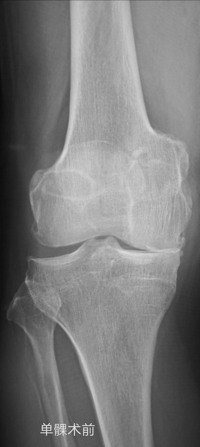

下面就有两种手术的照片,请大家感受了解一下。如果您还有什么疑问,请您毫不犹豫的咨询熊奡大夫吧!